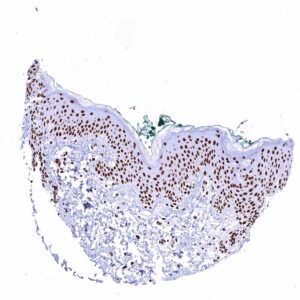

| Skin | Epidermis | Strong nuclear TRIM28 staining in all cells. |

In normal tissues, TRIM28 is ubiquitously seen in nuclei of all tissues.

Images describing the KAP1 / TRIM28 staining pattern in normal tissues obtained by the antibody HMV335 are shown in our “Normal Tissue Gallery”.